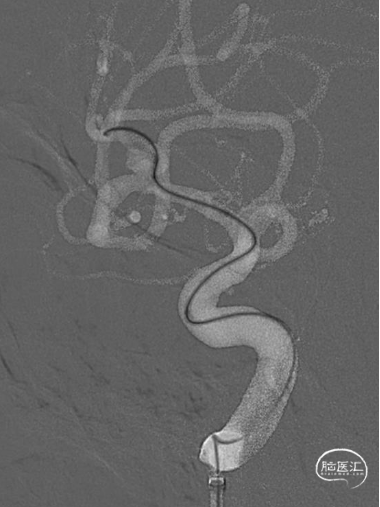

术前影像

CT显示广泛蛛网膜下腔出血,右侧侧裂池为著。

DSA示:右侧大脑中动脉分叉上干起始部宽颈动脉瘤,呈不规则分叶状,载瘤动脉管径纤细,角度锐利,载瘤动脉直径1.45mm,大脑中动脉直径2.26mm,动脉瘤大小约5.35mm×3.98mm×4.14mm。

术中全身肝素化,6F DA导引导管到达颈内动脉C1段远端,根据3D图像选取工作角度造影充分暴露载瘤动脉、瘤颈、动脉瘤长径。